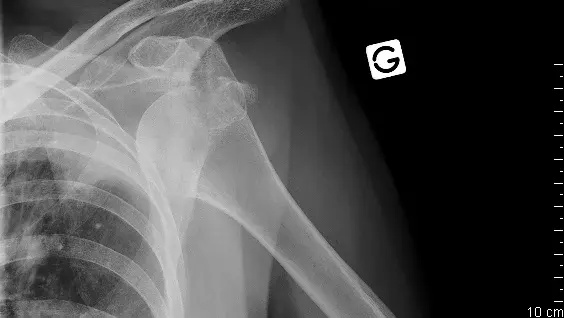

Die ist eine seltene Form der Instabilität. Sie kann auch im Rahmen einer neurologischen Erkrankung (Epilepsie) in Erscheinung treten oder auch als Folge eines Unfalles.

Auch hier spielen die Begleitverletzungen eine Rolle. Es sind die umgekehrte Hill-Sachs-Läsion (vordere Impressionsfraktur des Humerus) und die Bänderverletzung (Labrumläsion).

Auch hier kommt zuerst die nicht-operative Therapie zum Zug. Erst beim Versagen dieser Therapie können operative Methoden (arthroskopische Fixation der Bänder, Knochenblock) angewendet werden.